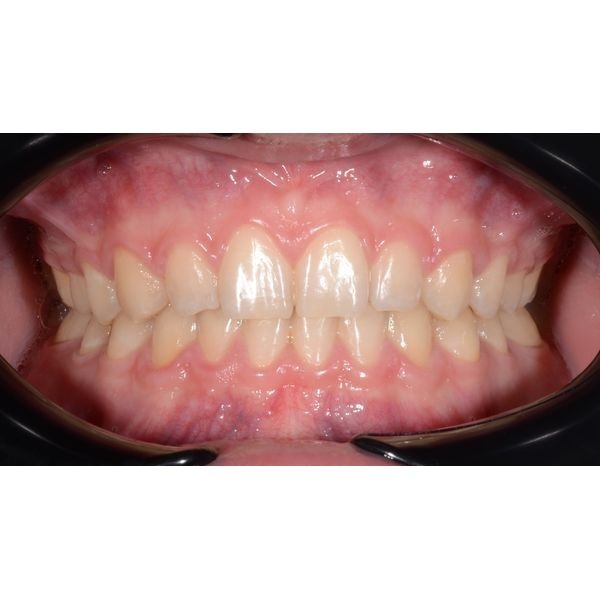

При осмотре наблюдалось:

- глубокое резцовое перекрытие зубов в переднем отделе;

- профицит (избыток) места на верхней челюсти;

- дефицит места на нижней челюсти;

- стираемость зубов.

В итоге лечение прошло без осложнений и в короткие сроки. Оно длилось 1 год 6 месяцев. За это время мужчине изменили глубину перекрытия зубов в переднем отделе, закрыли промежутки на верхней челюсти, создали плотные межзубные контакты в боковых отделах и исправили скученность зубов — достигли стабильной функциональной и эстетической окклюзии (плотного и правильного смыкания зубов).